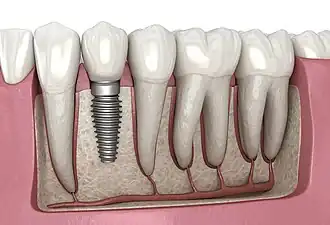

A dental implant (also known as an endosseous implant or fixture) is a prosthesis that interfaces with the bone of the jaw or skull to support a dental prosthesis such as a crown, bridge, denture, or facial prosthesis or to act as an orthodontic anchor. The basis for modern dental implants is a biological process called osseointegration, in which materials such as titanium or zirconia form an intimate bond to the bone.[1] The implant fixture is first placed so that it is likely to osseointegrate, then a dental prosthetic is added. A variable amount of healing time is required for osseointegration before either the dental prosthetic (a tooth, bridge, or denture) is attached to the implant or an abutment is placed which will hold a dental prosthetic or crown.

Single tooth implant restoration

Single tooth restorations are individual freestanding units not connected to other teeth or implants, used to replace missing individual teeth.[23] For individual tooth replacement, an implant abutment is first secured to the implant with an abutment screw. A crown (the dental prosthesis) is then connected to the abutment with dental cement, a small screw, or fused with the abutment as one piece during fabrication.[28]: 211–232 Dental implants, in the same way, can also be used to retain a multiple tooth dental prosthesis either in the form of a fixed bridge or removable dentures.